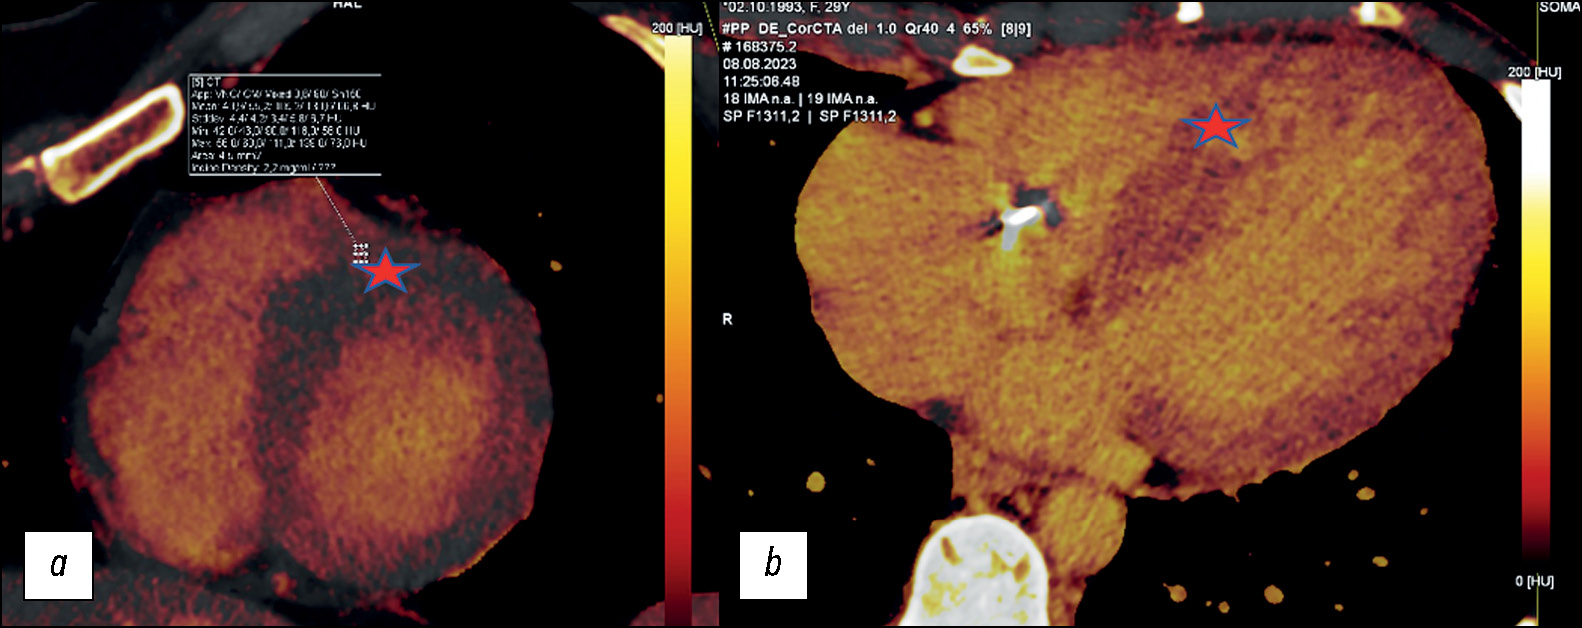

Вторая (отсроченная) фаза сканирования была проведена через 7 минут после ангиографической фазы для оценки структурных изменений миокарда ЛЖ. Область сканирования и поле обзора были скорректированы в соответствии с размером сердца для каждого пациента. По умолчанию, середина диастолы использовалась как фаза реконструкции с высоким и низким напряжением на трубке в аксиальной плоскости со следующими параметрами: толщина среза 0,75 мм, интервал 0,5 мм, фильтр реконструкции D30f. Построение йодных карт ДЭКТ проводили на рабочей станции (Syngo.via VB30A; Siemens Healthineers, Германия) с использованием приложения Heart PBV (perfused blood volume). Изображения отсроченной фазы сканирования были переформатированы в плоскость короткой оси с толщиной среза 8 мм и интервалом 0,5 мм (рис. 3).

Рис. 3. Йодные карты двухэнергетической компьютерной томографии: a — четырёхкамерная проекция сердца (ROI — измерение распределения йода в полости левого желудочка и межжелудочковой перегородке); b — короткая ось сердца (ROI — измерение распределения йода в полости левого желудочка и по межжелудочковой перегородке).

Оценка структурных изменений миокарда методом ДЭКТ выполнена 13 (27%) пациентам. У всех пациентов выявлены очаговые накопления йода на картах отсроченного контрастирования (рис. 8).

Рис. 8. Пример визуальной оценки очагового накопления йода в сегментах миокарда ого желудочка по данным йодной карты двухэнергетической компьютерной томографии: a — короткая ось сердца; b — аксиальная проекция сердца.

Зоны интрамиокардиального очагового накопления йода в 10 из 13 (76%) случаев локализировались по МЖП. Кроме того, на йодных картах отсроченного контрастирования проведен подсчёт фракции внеклеточного объёма (ECV) на среднем уровне ЛЖ. Значение ECV по данным йодных карт определялось следующим выражением:

В нашей работе у 10 из 13 (76%) пациентов отмечалось увеличение значения показателя в одном и более сегментах (N=25,4%). Среднее значение ECV миокарда ЛЖ по данным ДЭКТ составило 30,58% (95% доверительный интервал 27–34%) и превышало нормальные диапазоны.